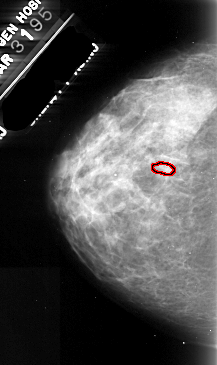

A_1105_1.RIGHT_CC

RIGHT_CC LINES 4381 PIXELS_PER_LINE 2671 BITS_PER_PIXEL 16 RESOLUTION 42 NON_OVERLAY

FILE: A_1105_1.LEFT_CC.OVERLAY

TOTAL_ABNORMALITIES 1

ABNORMALITY 1

LESION_TYPE CALCIFICATION TYPE PLEOMORPHIC DISTRIBUTION CLUSTERED

ASSESSMENT 4

SUBTLETY 2

PATHOLOGY MALIGNANT

TOTAL_OUTLINES 1

BOUNDARY